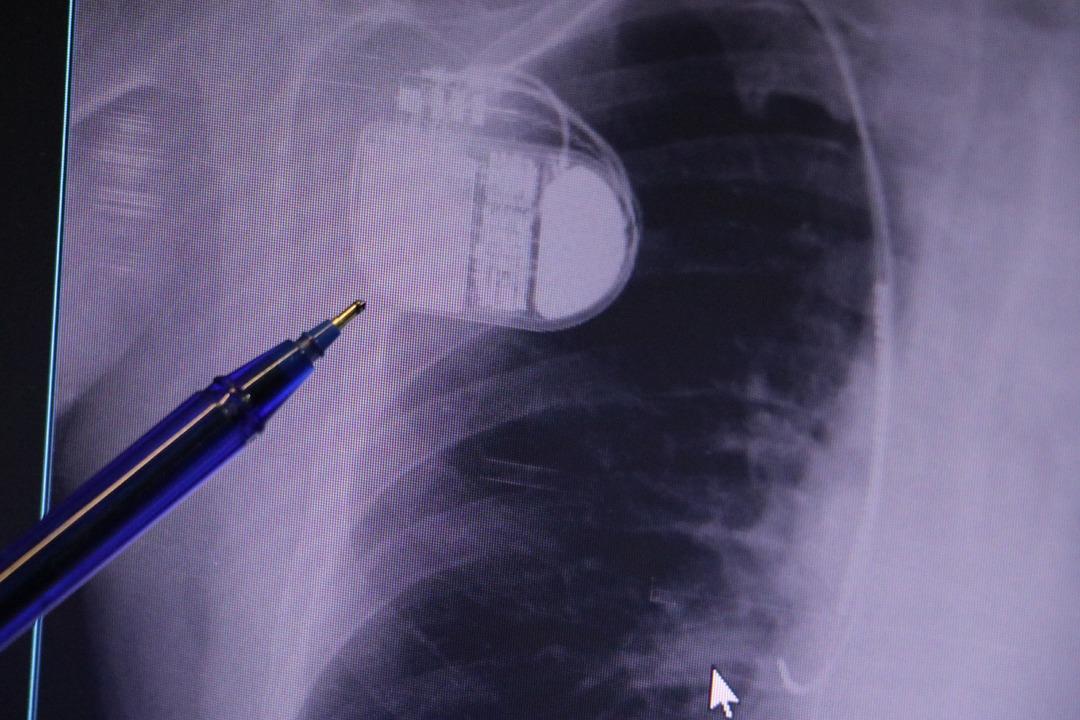

MR makinesine kalp pili takılmasının mümkün olduğunu belirten Erdoğu, şöyle konuştu: “Çok büyük bir ameliyat değil ama yine de ciddi bir cerrahi işlem. Kalp pili tıpta son 30 yılın en büyük gelişmesi. Aslında bilgisayarın minyatürleştirilmiş hali olup insan vücuduna yerleştirilen bir tedavi. İnsan ömrünü önemli ölçüde uzatan bir tedavi. İnsanlar şokla hayata tutunurken, pil olmasaydı öleceğini düşündüğümüz çok sayıda hastamız var. Bu özelliğimiz Kalp pili uygun hastalarda ani ölümü önler, ritmi düzeltecek sağlık çalışanı veya defibrilatör yoksa hastayı hayatta tutmak mümkün değildir. Hastalarımız “kalp pilim var” dediğinde hastalıktan kurtulurlar. Örneğin, mikser kullanmak veya kolu sallayacak herhangi bir hareket kalp pilini olumsuz etkileyebilir. Soğuk havalarda vücutta meydana gelen şiddetli titremeler kalp pilinin hafızasını karıştırıp gereksiz şoklara neden olabilir.